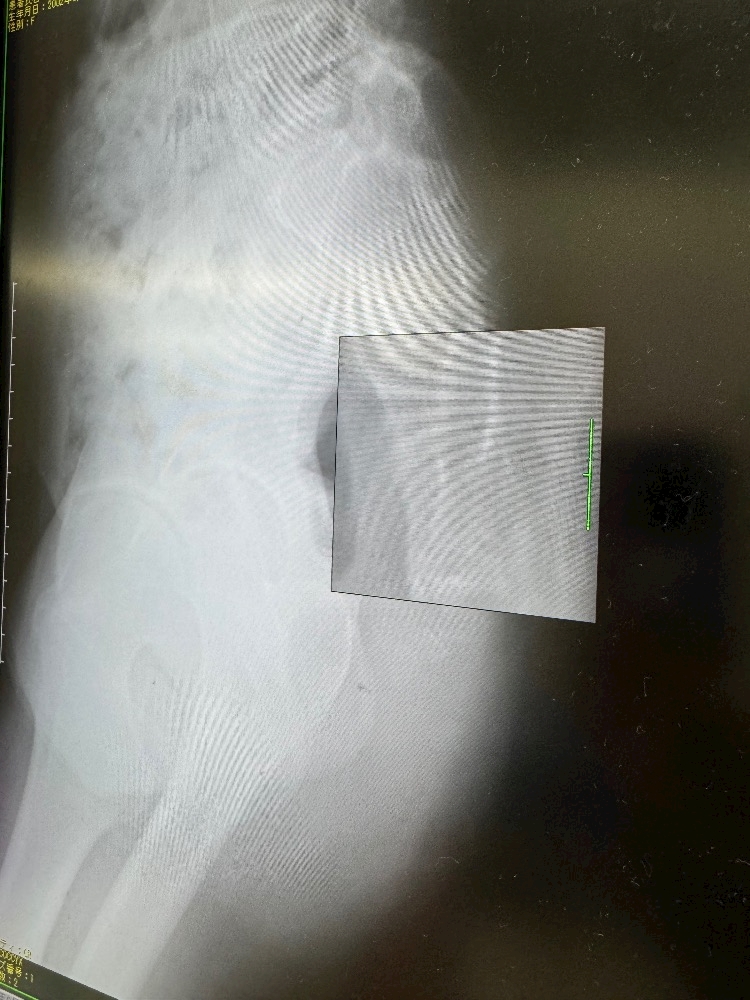

尾てい骨が痛すぎて

病院行ったら

尾てい骨に

ヒ ビ

入ってました〰️🦴